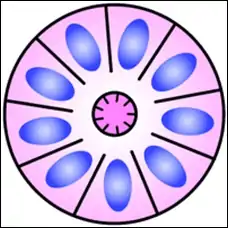

A rosette is a cell formation in a halo or spoke-and-wheel arrangement, surrounding a central core or hub. The central hub may consist of an empty-appearing lumen or a space filled with cytoplasmic processes. The cytoplasm of each of the cells in the rosette is often wedge-shaped with the apex directed toward the central core: the nuclei of the cells participating in the rosette are peripherally positioned and form a ring or halo around the hub.[2]

Loss or gain of genetic information is the main cause of rosette and pseudorosette formation. The cell populations exhibiting neuronal differentiation are believed to secrete surface glycoproteins and glycolipids which mediate cell-to-cell recognition and adhesion. One hypothesis is that these sticky cell surface markers cause the developing cell bodies to cluster or aggregate and their primitive neurites to tangle. As the cells grow, the neurite tangle remains centrally located and the cell bodies are squeezed to the periphery, thus explaining the rosette pattern. Depending upon their location, ependymal cells may display 2 cell poles. A luminal pole projects to the ependymal lining of a ventricle and a “submesenchymal pole” projects toward the surface of the brain demonstrating glial processes and peripherally situated footplates. Frieda and Pollak conceptualize the architecture of ependymomas as a primitive neural tube turned inside out with the submesenchymal poles converging toward a central vessel, thus forming a pseudorosette rather than projecting centrifugally toward the pia.[2]

Unlike the center of the Homer Wright rosette, the central lumen is devoid of fiber-rich neuropil. The defining feature of this rosette is central extension of cytoplasmic projections of the surrounding cells. Like the Homer Wright rosette, the Flexner–Wintersteiner rosette represents a specific form of tumor differentiation.[5][6][7][8] Electron microscopy reveals that the tumor cells forming the Flexner–Wintersteiner rosette have ultrastructural features of primitive photoreceptor cells.[9] Furthermore, the rosette lumen shows similar staining patterns as in rods and cones,[10] suggesting that Flexner–Wintersteiner rosettes represent a specific form of retinal differentiation. In addition to being a characteristic finding in retinoblastomas, Flexner–Wintersteiner rosettes may also be found in pinealoblastomas and medulloepitheliomas.[5]

Structure of a Flexner–Wintersteiner rosette

Structure of a Flexner–Wintersteiner rosette